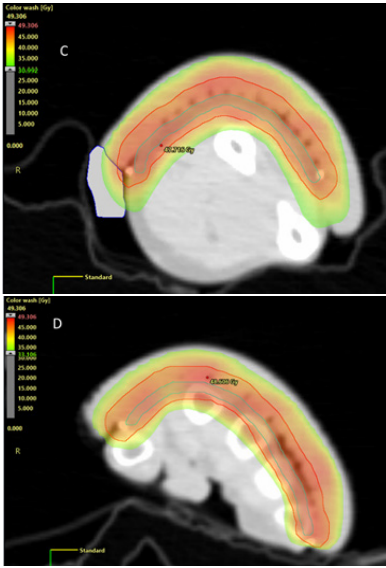

Volumetric modulated arc therapy (VMAT),14- 19 allows efficient definitive radiotherapy (RT) of convex SFC, such as over the nose, and also of ESFC commonly found over sun exposed scalps, foreheads, torsos, forearms, backs and legs (Figure 1). VMAT can treat large, long, yet thin convex shaped targets, as found in ESFC, with excellent conformality and homogeneity of dose and rapid fall off, and is superior to a brachytherapy moulds, matching electron fields or intensity modulated radiotherapy.14 Macroscopic invasive disease within these fields that may require more dose can be treated with a simultaneous boost technique (SIB) with VMAT.15

Figure 1

A. ESFC on left arm at presentation

B. Post VMAT showing resolution of ESFC

C. Axial dosimetry of VMAT at mid arm level showing conformal and homogeneous dose encompassing a convex target

D. Axial dosimetry of VMAT at level of hand showing the same as C.